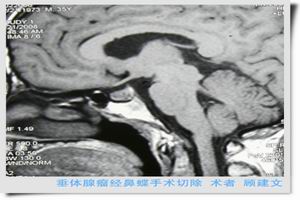

3.手術治療微腺瘤,可經蝶竇手術治療,腺瘤超過10mm如有下述指征需經顱手術。

(1)手術指征:①腫瘤向鞍上生長,視神經交叉受壓,下丘腦及第三腦室受壓引起腦積水等症狀者;②腫瘤向鞍前生長達到前顱凹額底者;③垂體卒中;④放射治療效果不滿意或惡化者;⑤有功能性或無功能性腺瘤產生臨床垂體功能亢進或減退者。

②治癒率PRL瘤為62%~90%,GH瘤為72%~89%,ACTH瘤70%~80%,Nelson征為44.4%。分泌性腺瘤術後長期隨訪復發率較高。